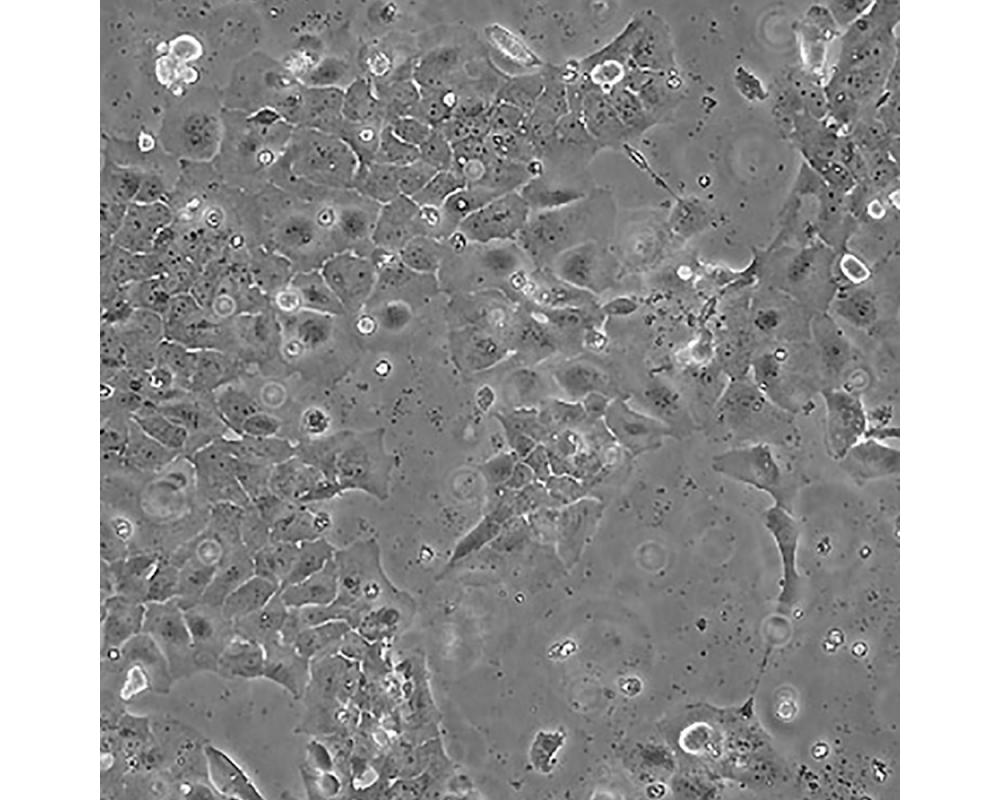

CAOV-3

中文名稱 人卵巢癌細胞

組織來源 卵巢癌;女性

形態特征 上皮樣

生長特性 貼壁生長